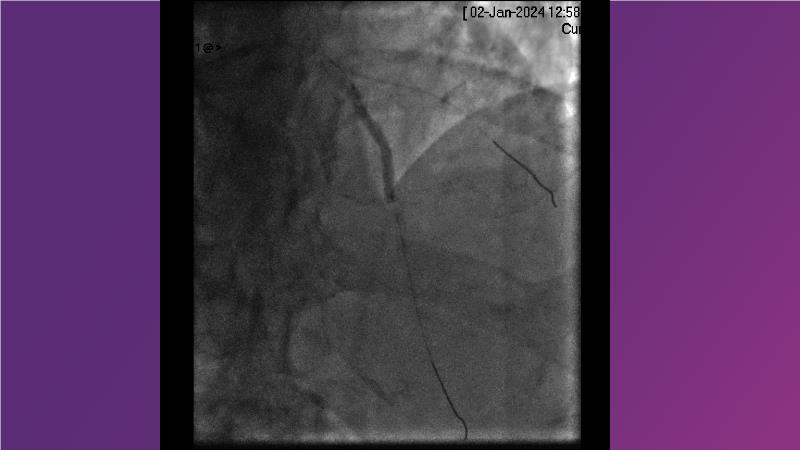

Sirolimus-coated balloon: exploring the case- and clinical-based evidences

Browse this EuroPCR 2024 session to explore the safety and efficacy of sirolimus-coated balloons from pre-clinical data, review MagicTouch data from real-world populations with case-based examples, and learn about the MagicTouch sirolimus-coated balloon clinical programs. Discover insights and takeaways from the significance of the EASTBOURNE subgroups, and analyze the challenges and opportunities in PCI for diabetic patients.

- To learn from the real world registries and complex cases to understand the practical implications and potential of the device in diverse patient population